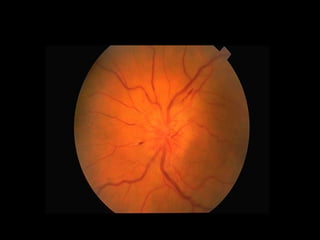

What will see in fundus?

Disc

Macula

Blood Vessels

Vein

Artery

Optic Disc

• The optic disc or optic nerve head is

the location where ganglion cell

axons exit the eye to form the optic

nerve

• The optic disc represents the

beginning of the optic nerve

• There are no light sensitive rods or

cones to respond to a light stimulus at

this point. This causes a break in the

visual field called "the blind spot" or

the "physiological blind spot".

Things to be seen: 3c

• Contour(Margin):

– The borders of the optic disc should be clear and

well defined

• Color:

– Typically the optic disc looks like an orange-pink

area with a pale centre. The orange-pink

appearance represents healthy, well perfused

neuro-retinal tissue

Cup:

As mentioned above

the disc has an

orange-pink rim with

a pale centre. This

pale centre is devoid

of neuroretinal tissue

and is called the cup

Arteries:

They are superficial, tortuous &

brighter. Normally arterial walls are

invisible, seen as streak, when light is

focused bright streak light reflexion is

seen.

• Veins :

They are thick, deeper & darker. Normally

venous pulsation is visible near the disc.

• Total vessels count in disc : 7-10, which

include vein & artery. Count only the main

vessels not the branches.

• Normal vein : artery = 3:2.